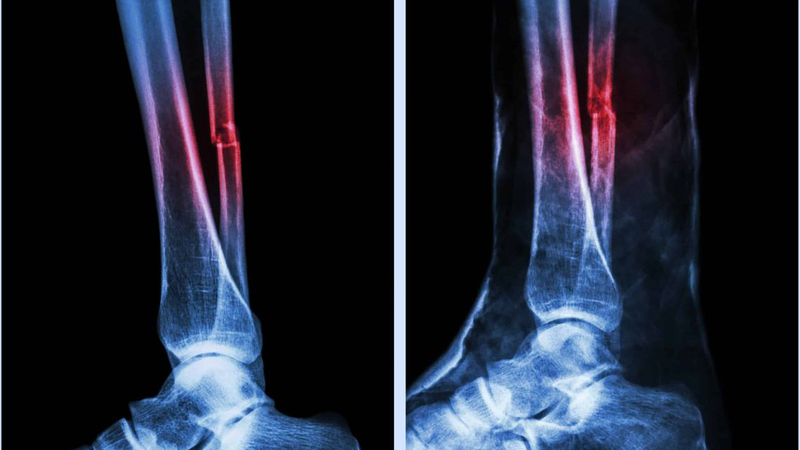

Xương mác là xương nhỏ, dài nằm song song với xương chày ở cẳng chân, có vai trò hỗ trợ và giữ vững khớp cổ chân. Khi đá bóng, va chạm mạnh dễ khiến xương mác bị gãy. Một trong những thắc mắc phổ biến của những người phải tạm rời xa sân cỏ vì chấn thương này là có thể đá bóng lại khi xương lành không. Câu trả lời cho thắc mắc này là có, nhưng cần đúng thời điểm.

Gãy xương mác bao lâu thì lành? Với một số gãy xương mác đơn giản, giai đoạn liền xương ban đầu có thể hoàn thành trong khoảng 6 - 8 tuần. Nhưng để trở lại luyện tập nặng, chạy, đổi hướng hoặc thi đấu thường cần lâu hơn thường vài tháng (thường 3 - 6 tháng) tùy loại gãy, điều trị và tiến triển phục hồi chức năng.

Để sớm đá bóng trở lại, người bị chấn thương không nên bỏ ngang phác đồ điều trị, luôn tái khám theo lịch để bác sĩ đánh giá mức độ liền xương qua X-quang. Điều này giúp phát hiện sớm các biến chứng gãy xương như lệch xương, nhiễm trùng hoặc chậm liền, tránh kéo dài thời gian hồi phục.